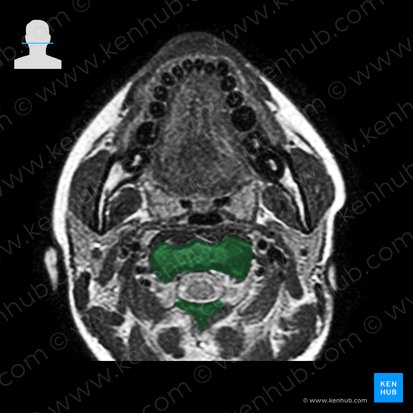

Der oberste Halswirbel (C1), der Atlas, unterscheidet sich von allen anderen Wirbeln dadurch, dass er keinen Wirbelkörper hat. Stattdessen besteht er aus zwei Seitenmassiven (Massae laterales), die über einen vorderen und hinteren Bogen (Arcus anterior et posterior) verbunden sind und gemeinsam das Foramen vertebrale bilden.

Die Massae laterales besitzen oben und unten jeweils Gelenkflächen. Der vordere Bogen hat in der Mitte ein Höckerchen (Tuberculum anterius) und innen eine Gelenkgrube (Fovea dentis) für den Zahn der Axis. Der hintere Bogen besitzt ebenfalls ein mittig liegendes Höckerchen (Tuberculum posterius), das jedoch schwächer ausgeprägt ist. Seitlich am Atlas entspringen die Processus transversi mit den Foramina transversaria.

Der Atlas und die Axis bilden das Atlantoaxialgelenk (Articulatio atlantoaxialis), auch unteres Kopfgelenk genannt. Dieses hat drei Anteile: Lateral verbinden sich die zwei Processus articulares superiores der Axis mit den zwei Facies articulares inferiores des Atlas (Articulationes atlantoaxiales laterales). Beim dritten handelt es sich um ein Drehgelenk zwischen dem Dens axis und der dorsalen Fläche des vorderen Atlasbogens (Articulatio atlantoaxialis mediana).